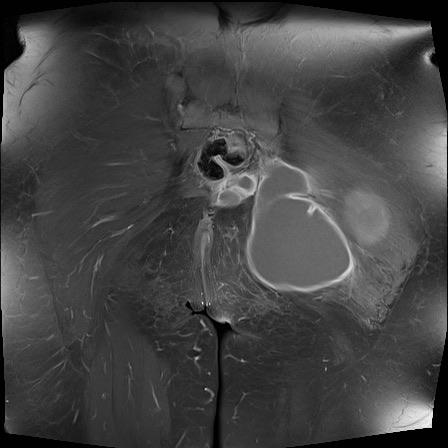

MRI

MRI chuỗi xung T1W sau tiêm thuốc tương phản từ của cùng bệnh nhân cho thấy bờ khớp cùng chậu không đều do bào mòn.

Có ngấm thuốc ở xương dưới sụn và phù nề tủy xương.

Không có tràn dịch khớp.

Thuốc tương phản từ tiêm tĩnh mạch không nhất thiết phải sử dụng để chẩn đoán viêm khớp cùng chậu.

Cuộn qua các hình ảnh MRI và so sánh với các dấu hiệu trên X-quang (hình ảnh cuối cùng).